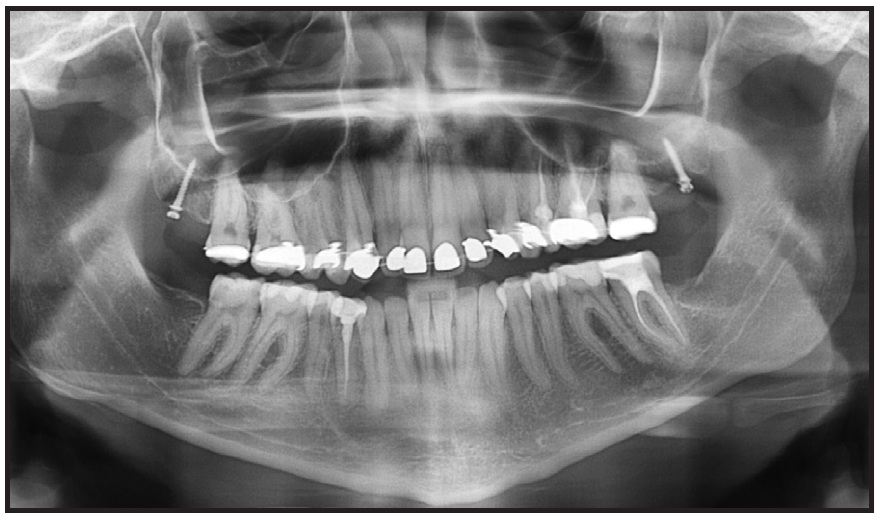

In less than a year of treatment, the anterior open bite was closed and the molar Class II malocclusion improved, but a posterior open bite had been created (Fig. 4A). Comparing the initial panoramic x-ray and a progress x-ray taken at that time, there was a considerable reduction in the distance between the upper second molars and the mini-implants, demonstrating a bodily maxillary retraction.

Fig. 4 After 10 months of distalization. A. Distance between miniscrews and second molars reduced substantially and Class II malocclusion improved, but posterior open bite created due to direction of forces. B. Power chain passed buccally over molar tubes to help control bodily movement and prevent undesirable vertical movement.

The posterior left crossbite and right edge-to-edge bite had been corrected by applying a bit more force from the lingual side, allowing expansion of the maxillary teeth to resolve the anteroposterior and transverse problems. As planned, there was a substantial amount of posterior intrusion. This changed the open bite from anterior to posterior; in other words, the divergence between the upper and lower occlusal planes had shifted to a convergence of planes. Because the distalization force was applied from the mini-implant in the tuberosity to the bracket at the crown level, distal crown tipping was inevitable. Bodily movement was achieved by passing the buccal chain over the molar tubes, creating a downward force, and by increasing the size of the lingual archwire (Fig. 4B). Incognito has an advantage in this respect because it uses a ribbon arch instead of an edgewise wire. Additionally, because the archwire has a large vertical cross-section, it compensates for the tipping effect by filling the bracket slot.

Anterior and posterior intrusion was required to reduce the gummy smile and make the upper and lower occlusal planes parallel, thus allowing more mandibular autorotation. Two Dual-Top JA standard mini-implants (1.4mm x 6mm) were inserted between the upper lateral incisors and canines (Fig. 6).

Fig. 6 After 16 months of treatment, two Dual-Top mini-implants placed between roots of upper lateral incisors and canines, composite buttons bonded to labial surfaces of canines, and power chain applied from miniscrews to buttons.

Composite buttons were bonded to the labial surfaces of the canines, and power chain was attached from the miniscrews to the buttons. Simultaneous traction was applied to the four implants to intrude both the anterior and posterior maxillary dentition. After seven months of intrusion on both sides, traction was applied only to the right implants, especially the anterior one, to further intrude the incisors on that side while eliminating the maxillary cant (Fig. 7). The elastic chain was changed less often to maintain movement as long as possible and prevent relapse.18